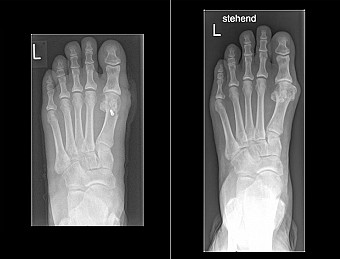

OP nach Chevron vorher und nachher

Bei einer Untersuchung prüft der Fußchirurg oder Orthopäde zunächst durch Abtasten und Anschauen des Fußes, wie stark dieser belastet ist. Es sollten stets beide Füße untersucht werden, denn nur so erhält man Hinweise auf Abweichungen und darauf, wie stabil oder instabil ein Patient auf seinen Füßen steht. Ein Blick auf dessen Schuhe oder Einlagen lässt weitere Rückschlüsse zu und die anschließende Röntgenaufnahme, auch unter Belastung des Fußes, führt schließlich zur exakten Diagnose.